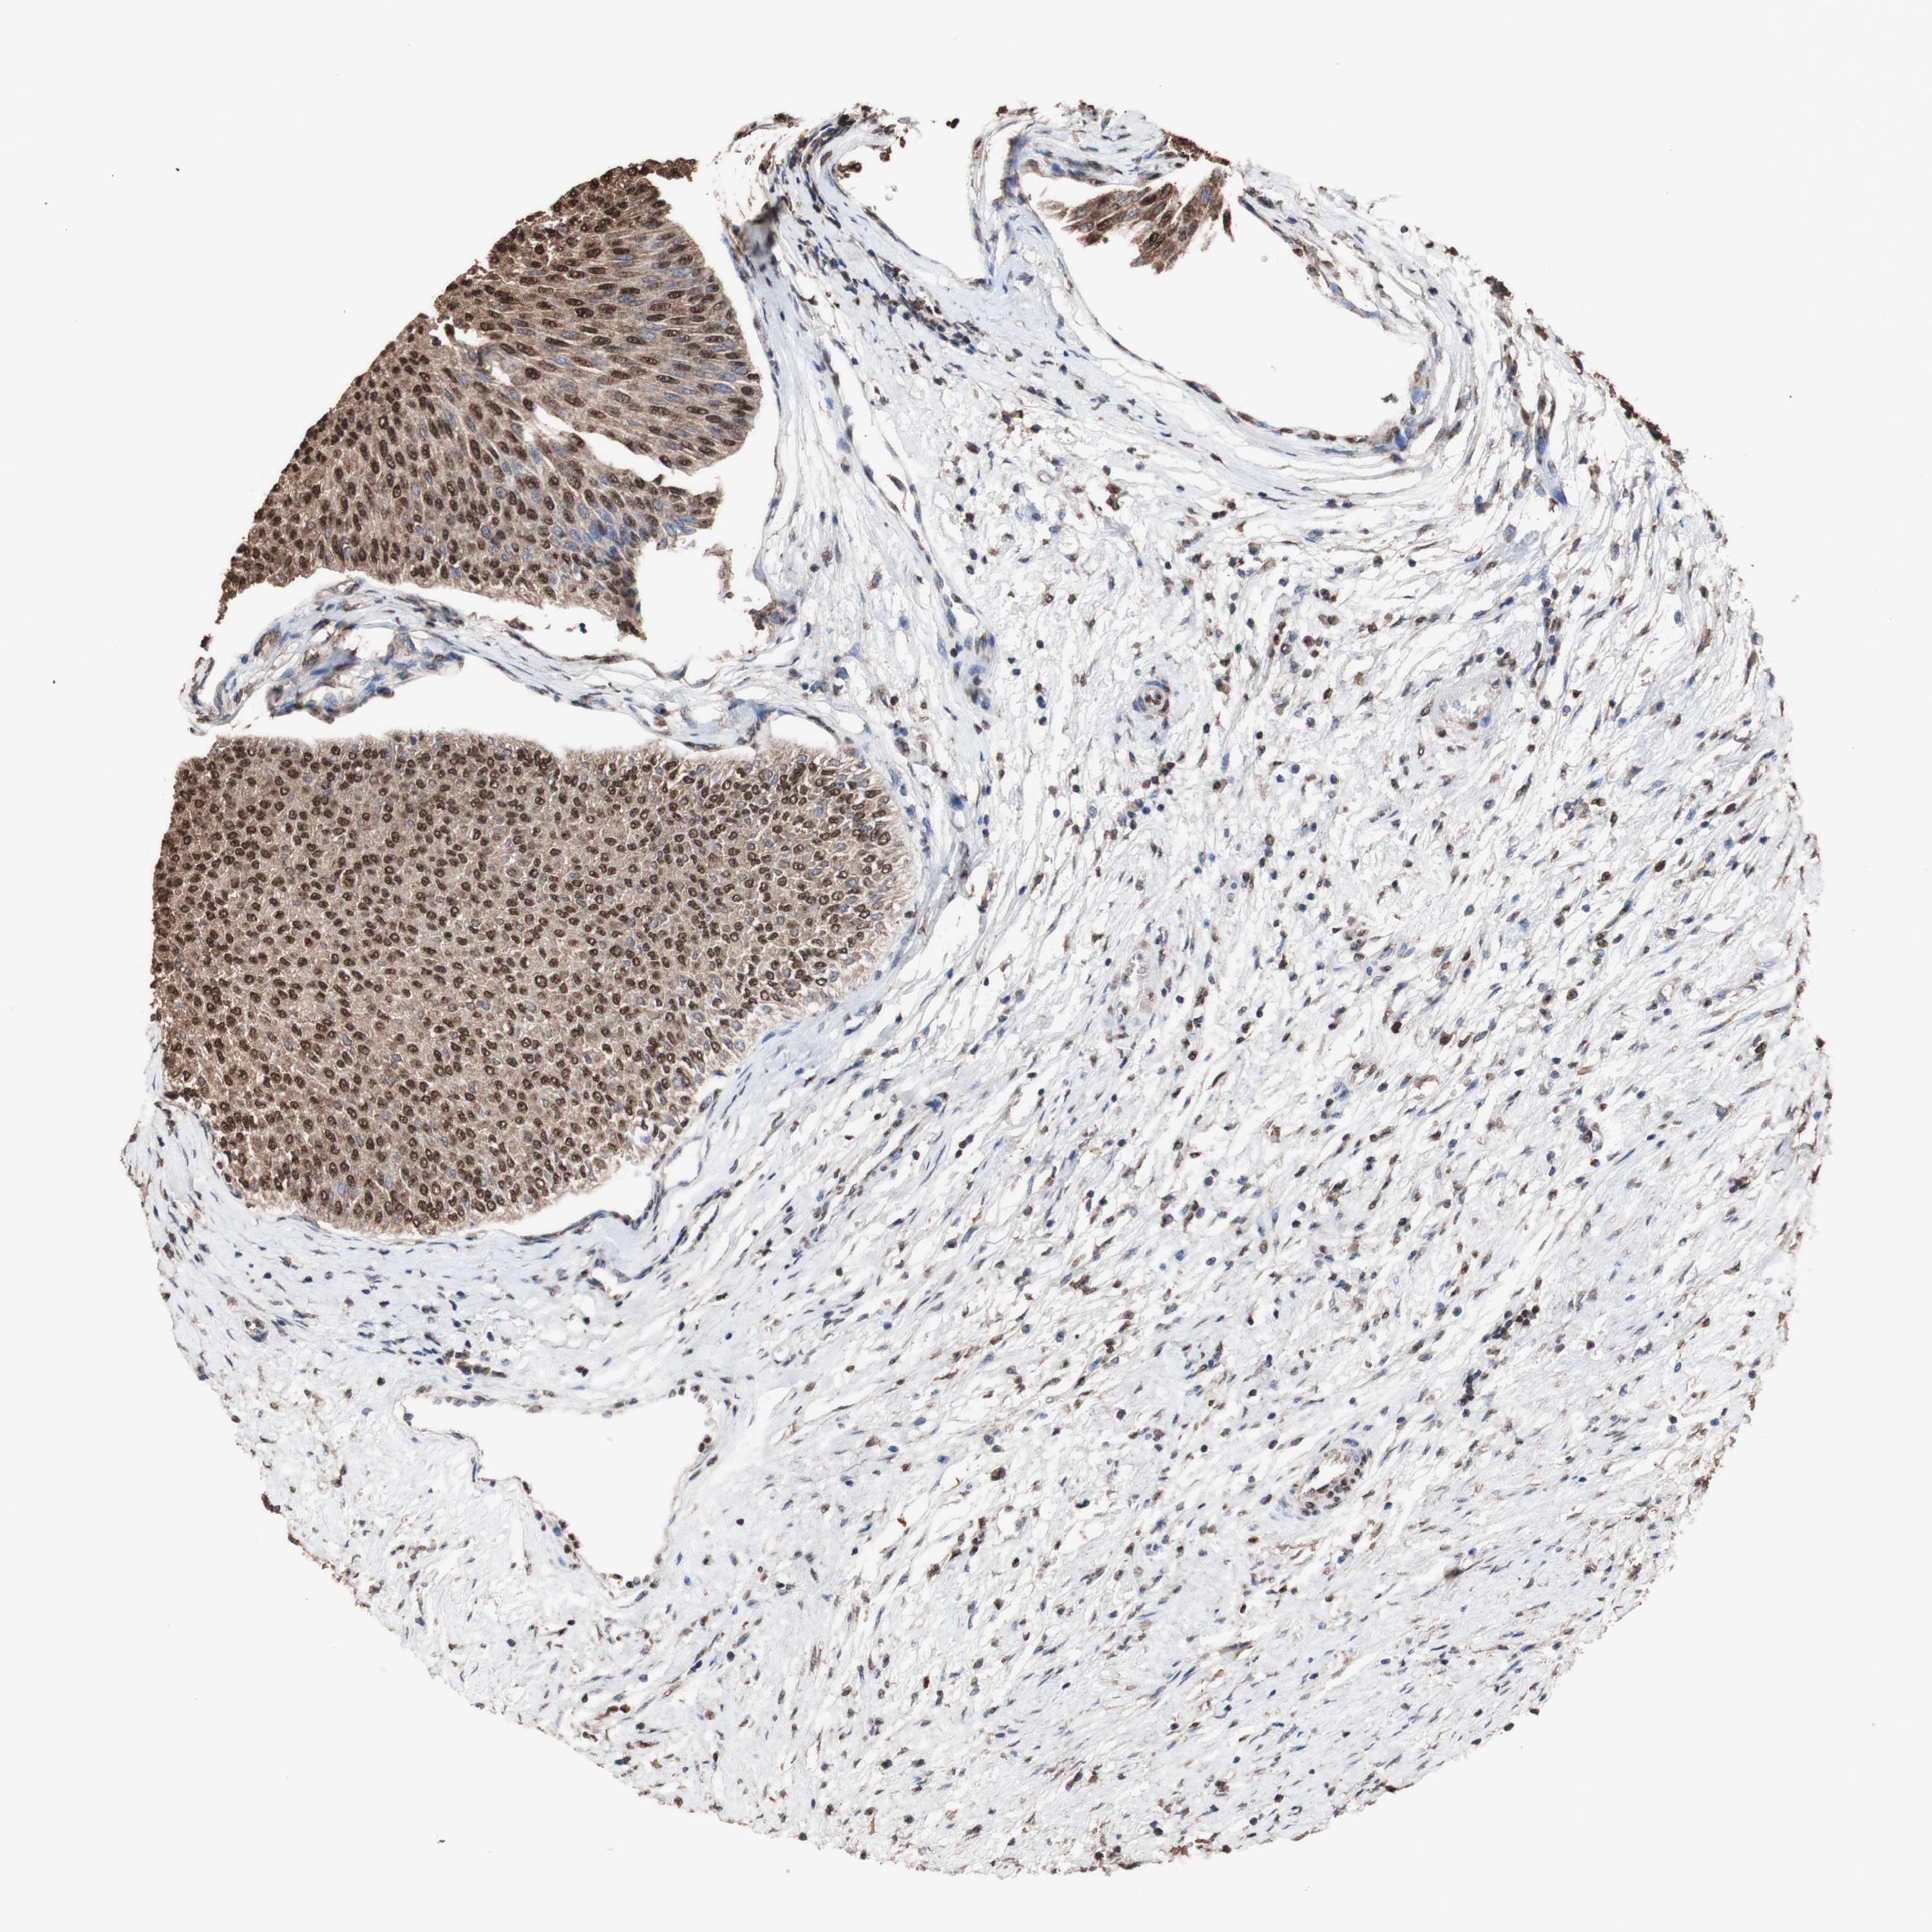

UROTHELIAL CANCER - Protein expressioni

A mouse-over function shows sample information and annotation data. Click on an image to view it in a full screen mode. Samples can be filtered based on level of antibody staining by selecting one or several of the following categories: high, medium, low and not detected. The assay and annotation is described here.

Antibody stainingi

Antibody staining in the annotated cell types in the current human tissue is reported as not detected, low, medium, or high, based on conventional immunohistochemistry profiling in selected tissues. This score is based on the combination of the staining intensity and fraction of stained cells.

Each image is clickable and will lead to virtual microscopy that enables deeper exploration of all samples and also displays staining intensity scores, fraction scores and subcellular localization as well as patient and tissue information for each sample.

Antibody HPA066948

Antibody CAB012647

Urothelial carcinoma, High grade

Urothelial carcinoma, NOS

Urothelial carcinoma, Low grade